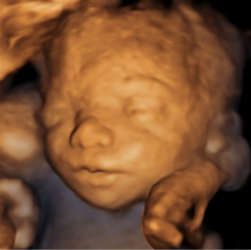

四维超声检查(动态三维超声检查)只是给宝宝拍了一张照片,对胎儿位置和姿势要求较高,胎儿孕周比较大才能拍的好,不能够评价胎儿的结构和发育情况。如果要求了解宝宝的结构是否正常,只需要选择系统产前超声检查。

点击这里看看四维彩超里的萌宝//v.qq.com/page/u/8/9/u03089v9w89.html